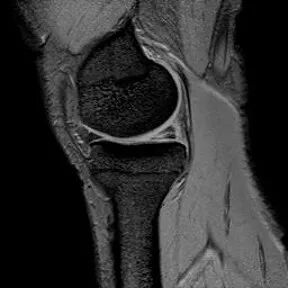

半月板斜行撕裂

最常见类型:斜行撕裂表现为:在矢状面上见III级高信号到达半月板关节面的上缘或下缘